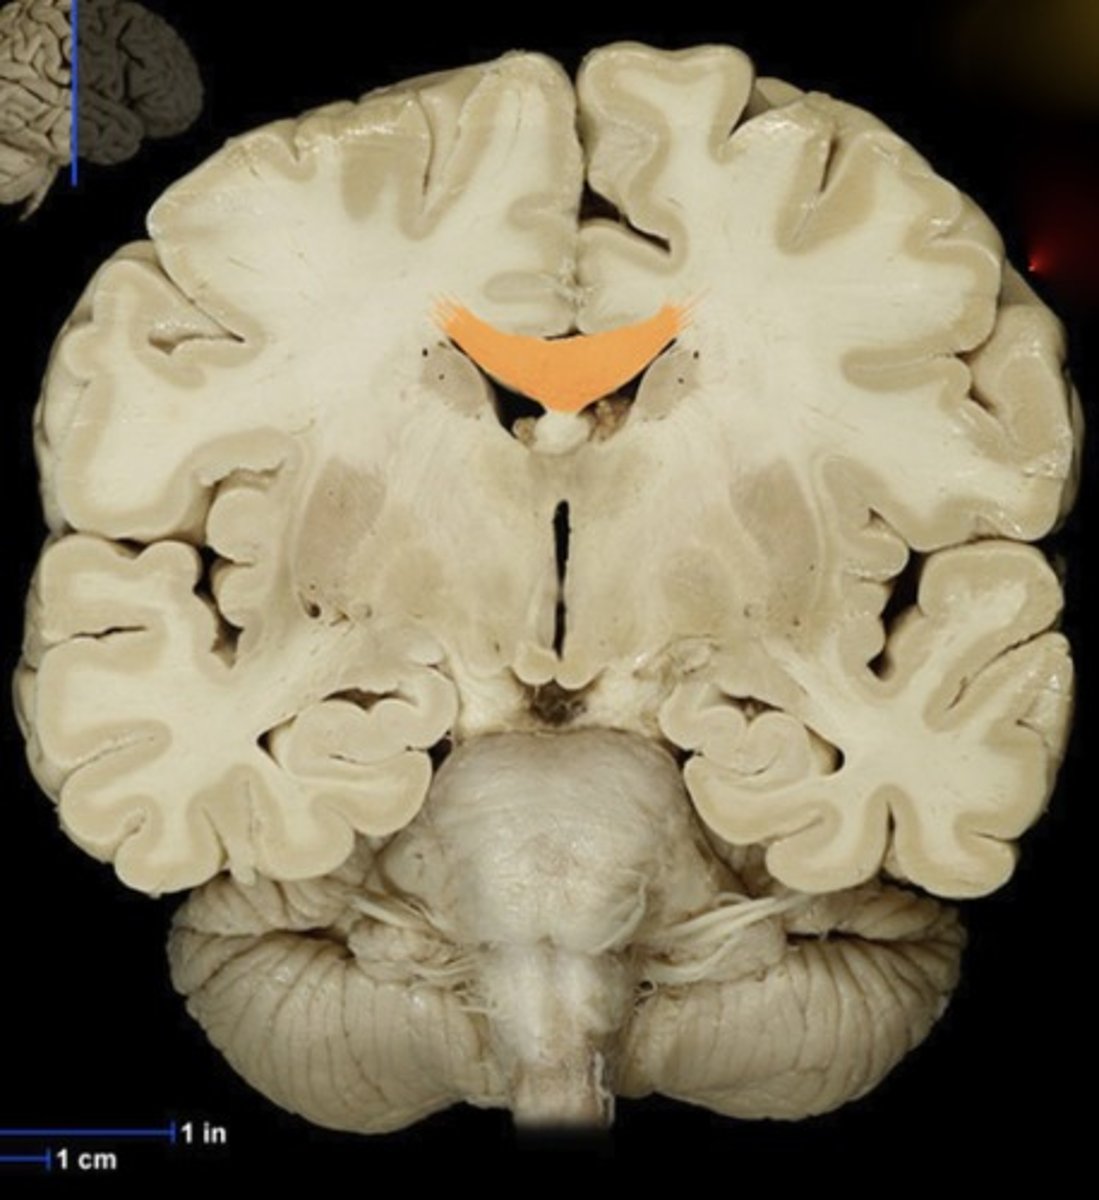

Name this structure

Corpus callosum

Name this structure

Fornix

Name this structure

Globus Pallidus